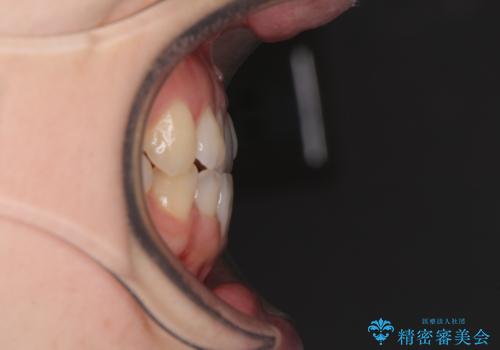

前歯のクロスバイト インビザラインによる矯正治療

- 前歯のクロスバイトとデコボコを気にして来院された患者様です。

インビザラインを用い、下顎歯列を後方に移動させながら全市の被蓋を改善し、歯並びを整えていくこととしました。